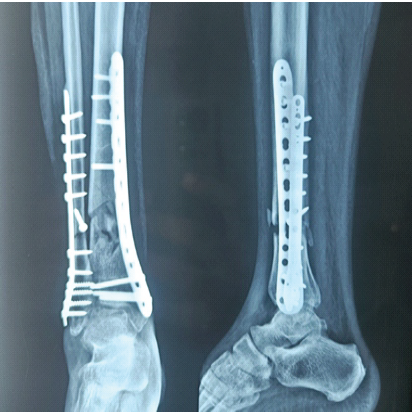

A 65-year-old male patient met with a road traffic accident and sustained a Gustilo Anderson Type-3A fracture of tibia with bone exposed. On radiology, it is of AO 42A3 fracture, that is, extra-articular distal tibial fracture with metaphyseal comminution (Fig. 1). He was treated at a different center initially with debridement and primary fixation with anteromedial fixation with distal tibial LCP and fibula is fixed with a one-third tubular plate (Fig. 2).

Figure 2: Immediate post-operative X-ray after initial fixation.